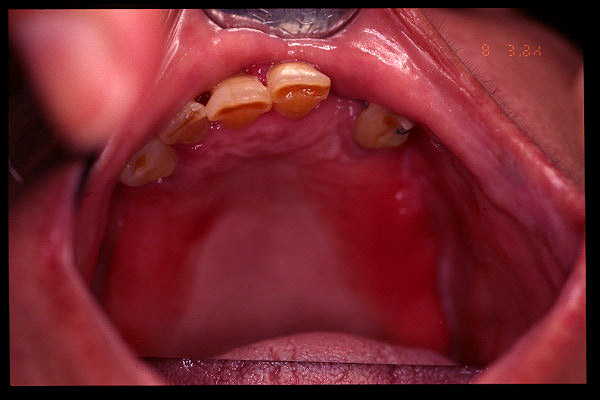

CM Unicos dientes remanentes: caninos superiores